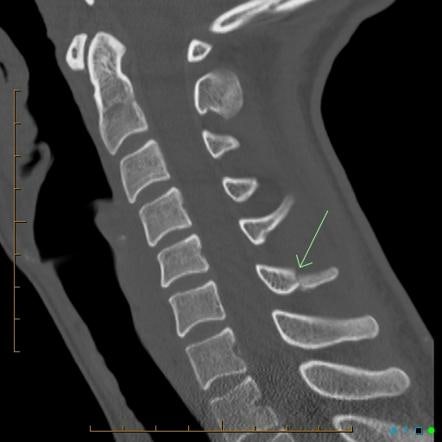

안녕하세요 대구경북(용천, 경산, 경주, 포항, 영덕, 울진, 안강, 왜관, 칠곡, 상주, 금천, 성주, 고령, 안동, 영주, 봉화, 치구) 손해사정사, 손해사정사 Harden Loss Adjustment 입니다. 오늘은 트라우마로 인한 십자돌과 돌기둥의 후유증에 대해 알아보도록 하겠습니다. 횡돌기 또는 횡돌기는 척추 양쪽의 척추 고리에서 확장되는 두 가지 구조로 낙상이나 교통사고와 같은 외상으로 인해 발생합니다. 가시돌기는 좌우 척추뼈가 융합되어 등쪽에서 아래쪽으로 돌출되는 과정입니다. 일반적으로 수술적 치료 대신 보존적 치료를 시행하며, 척추체 자체의 골절이 아니기 때문에 경미한 손상으로 간주되는 경향이 있습니다. 아래 사진에서 두 개의 날개처럼 보이는 것이 횡돌기이고 그 뒤에 가시돌기가 위치한다.

진단에 대한 인식과 환자의 현실 사이에는 불일치가 있습니다. 비수술적 보존적 치료를 하면 바로 입원할 수 있을 만큼 쉬운가요? 그래도 후유증은 정확히 확인해야 한다. 경추, 흉추, 요추의 해당 부위와 골절 정도(다발골절 등), 골절의 종류에 따라 일시적 장애 적용 범위는 18%~24%로 추정 McBride 손실률 테이블. 치료 중에는 활동적이고 집중적인 자세를 유지해야 합니다. 횡돌기 및 극돌기 골절에 대해 궁금하신 사항이 있으시면 아래 링크를 클릭 또는 탭하시면 상담이 가능합니다.